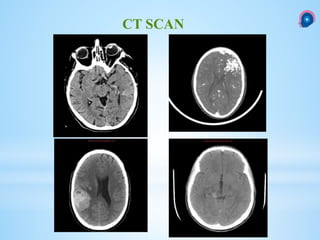

 Intracranial hemorrhage.

 Suspicion of an AVM.

 calcium deposition (25% to 30% )

 Iso- to hyperdense serpiginous vessels that might be located at some distance from the

hemorrhage.

 A CT angiogram (CTA) : delineate the nidus and associated vessels.

CT SCAN